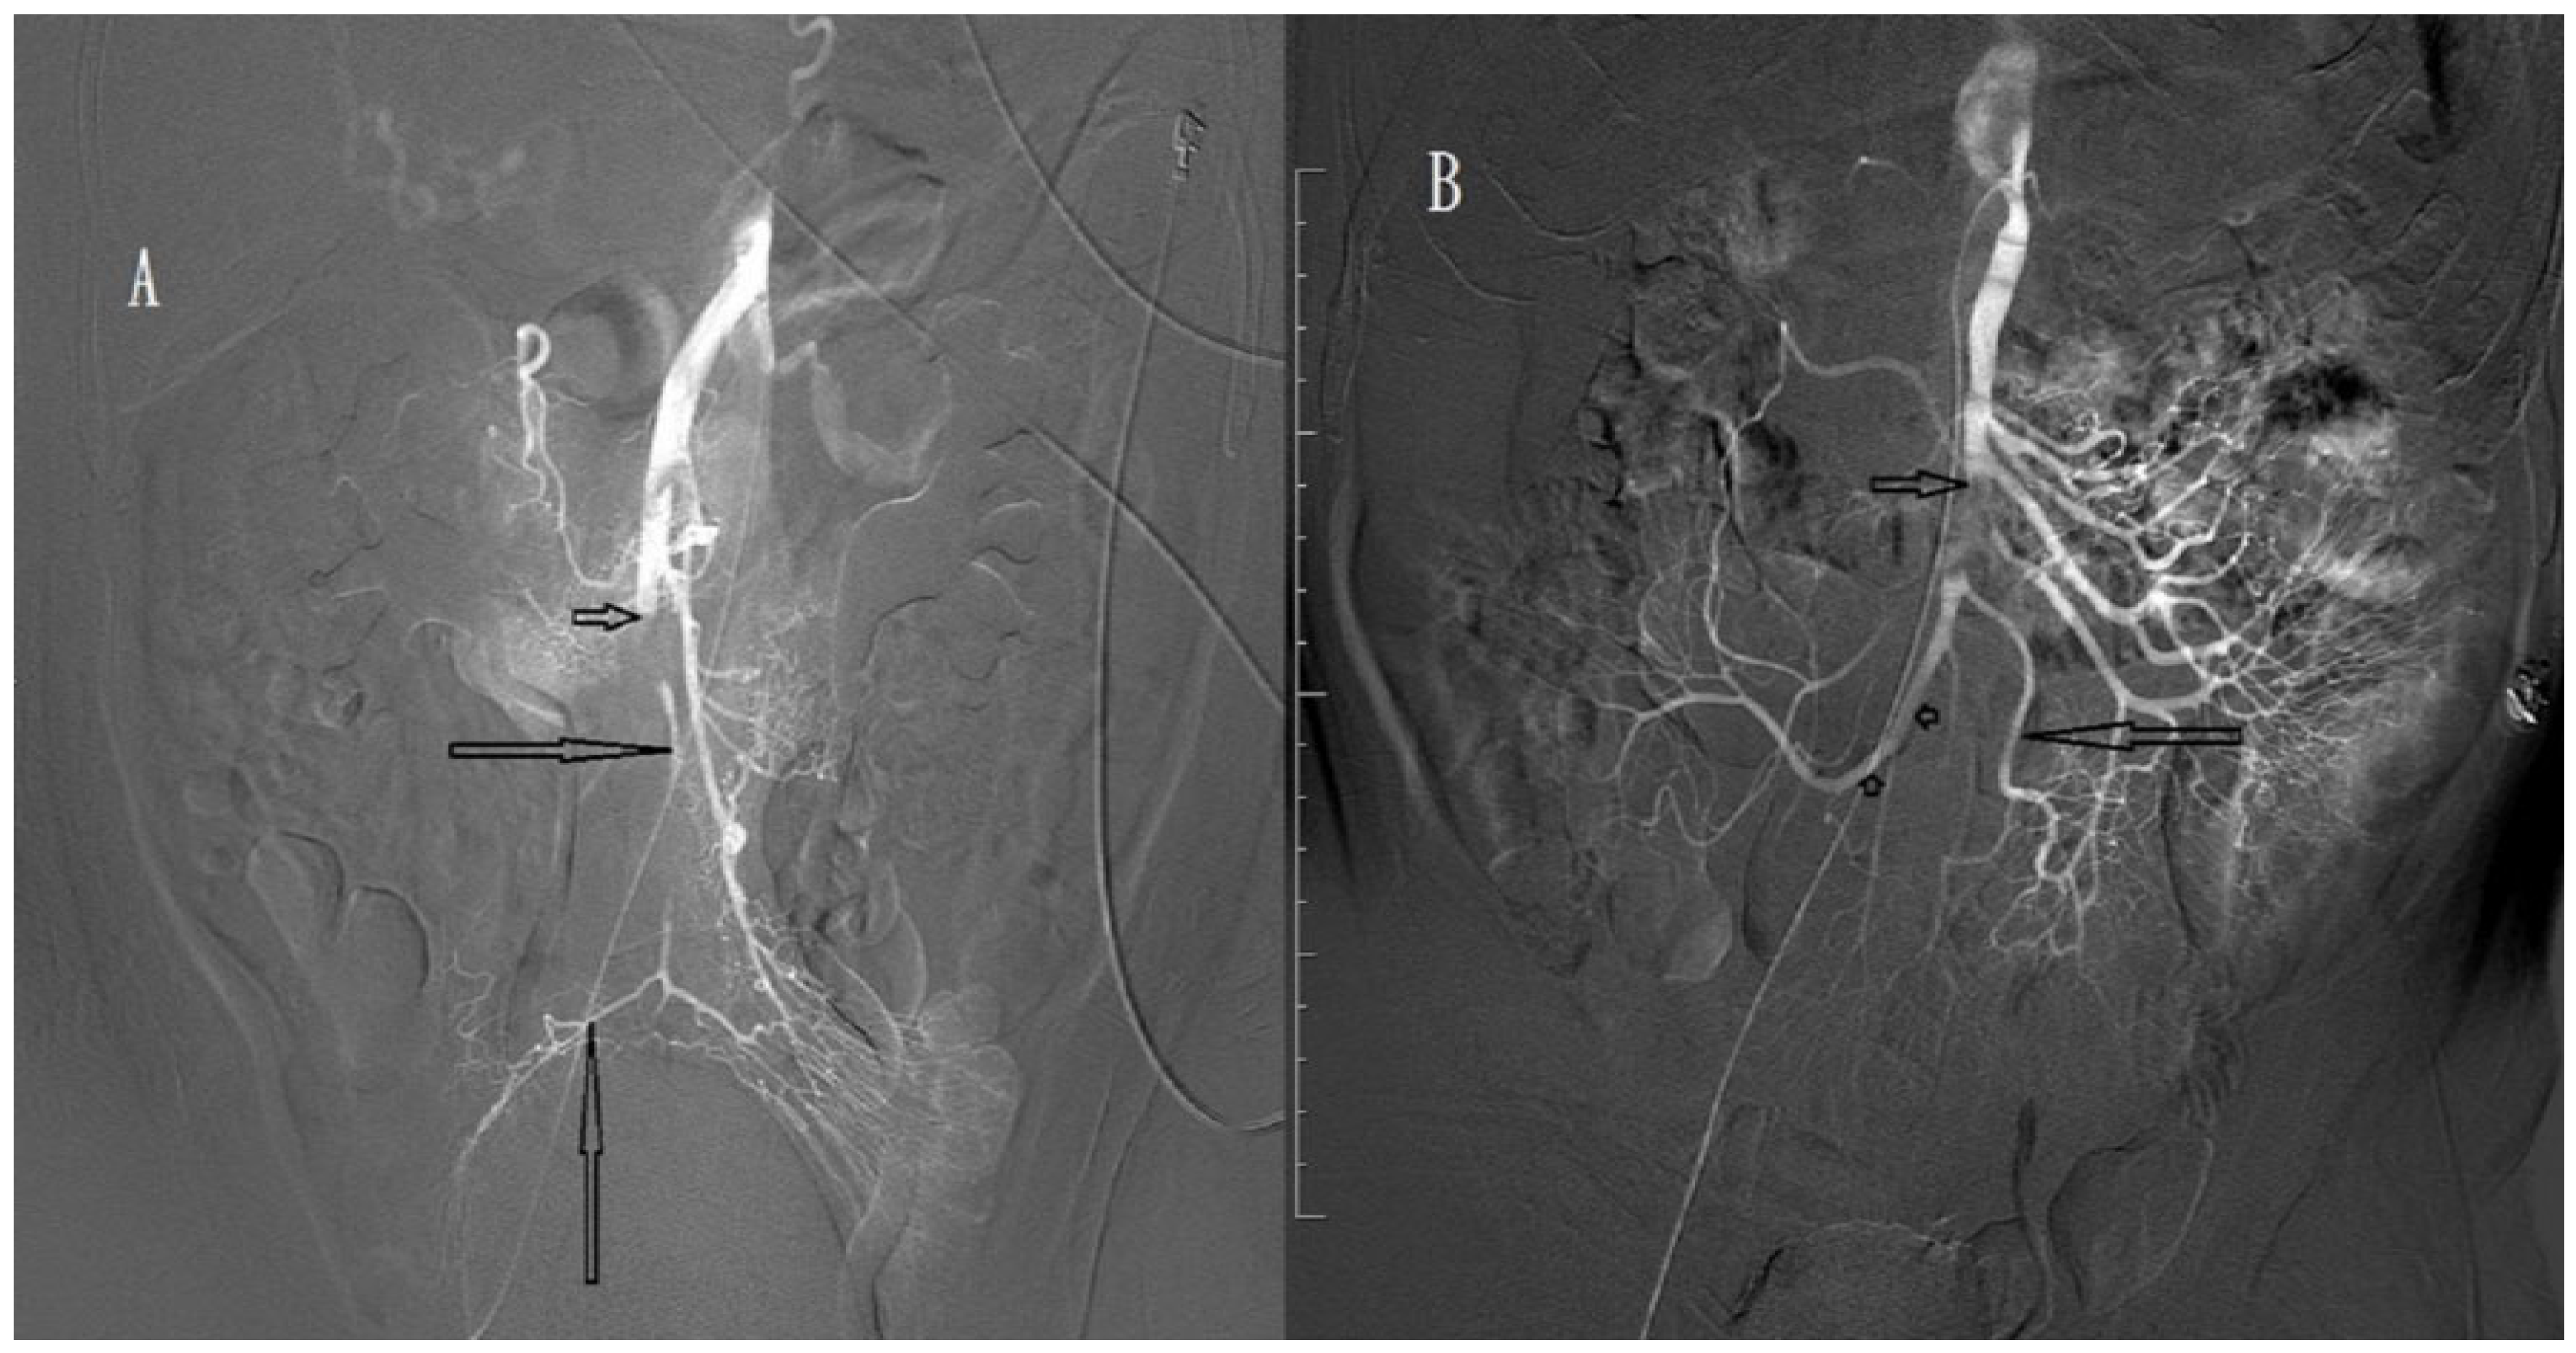

2.4. Procedure